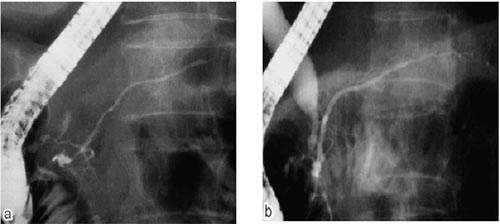

图a:胰管狭窄 图b:治疗后狭窄的胰管恢复正常